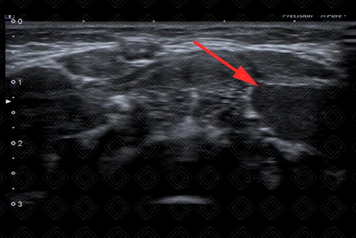

Texto alternativo para a imagem Figura 1. Créditos: Dra. Elazir Mota - Rio de Janeiro/RJ

Descrição das figuras 1 e 2: Ultrassonografia cervical evidenciando lesão cística, predominantemente hipoecoica, no espaço sublingual esquerdo, herniando através de uma falha no músculo milo-hiodeo (setas vermelhas), compatível com rânula simples.

• Ultrassonografia cervical: Imagem anecoica/hipoecoica, de paredes finas, bem definida, acima do músculo milo-hioide, no assoalho da boca. A lesão pode apresentar grumos de debris no seu interior e aumento da ecogenicidade do tecido subcutâneo adjacente, quando infectado (figura 1);